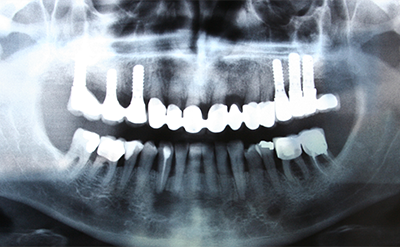

歯科用CT

歯や顎の骨の状態や、神経の位置などを立体的に撮影できる装置です。お口全体を正確に把握することができ、より安全で確実な治療を可能にします。